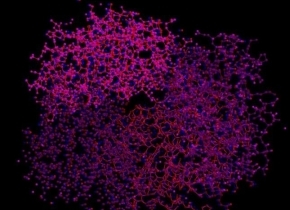

血红蛋白的分子结构